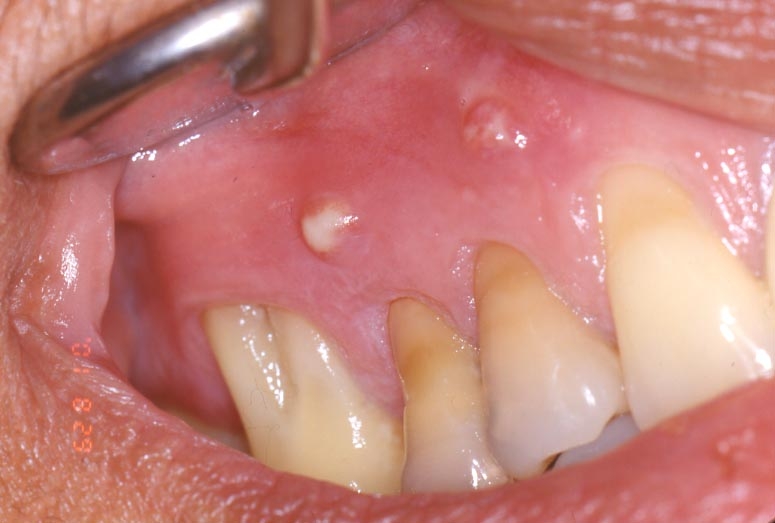

- Pimples on the gums

- Swollen or tender gums

- Deep decay or darkening of the gums